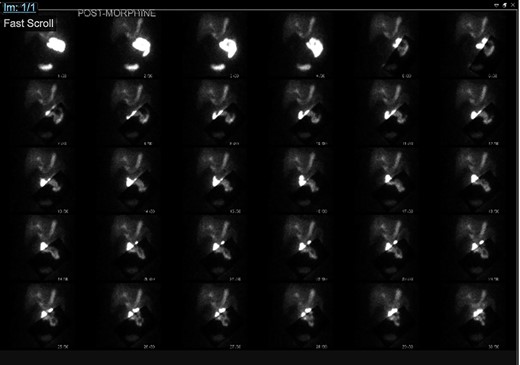

The patient returned to the clinic 2 years later due to continued pain, located over the epigastric, right upper and right lower aspects of her abdomen. She underwent the HIDA scan with 5-mCi Choletec, which demonstrated a non-visualized gallbladder throughout the entire study even with the administration of 3.6-mg morphine, which were consistent with chronic cholecystitis. At her subsequent clinic visit, she continued to report right upper quadrant pain, which now radiated to the right side of her back worse after fatty food intake and with associated nausea. Because of her HIDA scan finding of cholecystitis and her continued symptoms, she was scheduled for an outpatient laparoscopic cholecystectomy.

Gallbladder agenesis is a rare anomaly in which an individual is born without a gallbladder. This phenomenon affects <0.1% of the population with only 400 cases documented in medical literature to this day [2, 3]. This anomaly is discovered incidentally during workups for symptoms consisting of gallbladder pathology as seen in our patient. Initial work up for a gallbladder pathology includes a right upper quadrant ultrasound and, in this patient, it showed a collapsed gallbladder around gallstones, as seen in Fig. 4. This pointed to a diagnosis of cholecystitis. A further look with a HIDA scan confirmed this diagnosis as it showed the absence of radiotracer entering the gallbladder even after the administration of morphine, seen in Figs 5 and 6. A non-visualized gallbladder typically occurs due a gallstone obstructing the passage of the radiotracer entering the gallbladder [4]. Gallbladder agenesis could cause this radiographic finding as well, however, this anomaly was low in our differential as the initial ultrasound showed a collapsed gallbladder and the patient’s absence of other medical conditions associated with gallbladder agenesis, such as Klippel–Feil syndrome, horseshoe kidney, malrotation of the gut or aberrant left pulmonary artery, none of which were suspected in our patient seen on examination and radiographically [1]. The normal location of the gallbladder is located on the undersurface of the liver, aligning with the intrahepatic line that separates the right and left hepatic lobe. There was no sign of this organ once the liver was elevated, seen in Fig. 1. The likely cause of this patient’s chronic right sided abdominal pain were the multiple abdominal adhesions, which were lysed.

HIDA scan showing normal extraction of radiotracer into the biliary tree with non-visualization of the gallbladder, pre morphine.